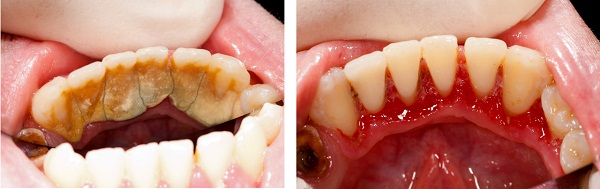

牙结石是口腔中常见的硬质沉积物,由牙菌斑矿化而成。牙结石长的快是为什幺?许多人发现自己的牙结石生长速度较快,这背后涉及多种因素。下面深圳爱康健口腔医院小编为大家详细介绍。

·定期专业维护:建议每6-12个月进行一次专业洁牙,及时清除已形成的牙结石,预防牙周疾病。

若已出现明显牙结石堆积、牙龈出血或牙齿松动等症状,建议及时就诊,接受专业评估和治疗。通过科学的日常护理和定期的专业维护,可以控制牙结石形成,维护口腔长期健康。